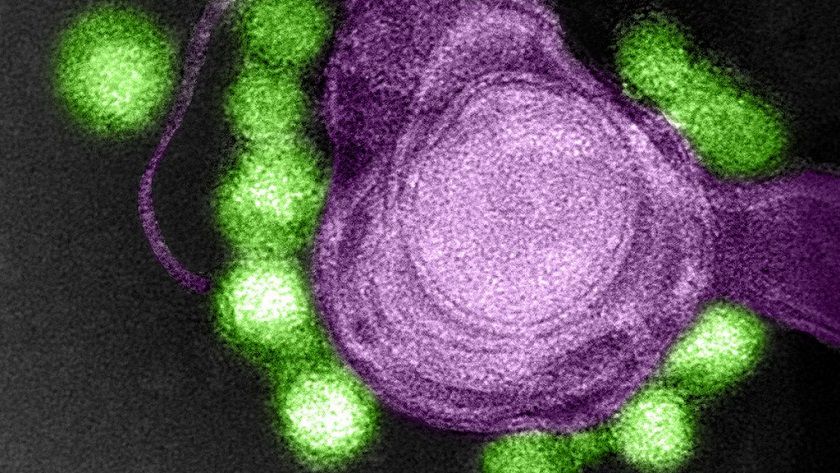

Hace ya más de un año que hablamos del virus Zika, un patógeno muy peligroso que provoca microcefalia. Sin embargo parece que podría ser muy útil a nivel médico, ya que según los expertos se puede utilizar para tratar casos de cáncer cerebral que se encuentran en una etapa muy avanzada.

Ahora que tenemos una idea base del cáncer cerebral y de los tratamientos básicos podemos entender el valor que plantea el virus Zika como tratamiento. Según los experimentos que han realizado un grupo de expertos dicho patógeno es capaz de atacar y destruir esas células madre que crean células cancerosas.

Esto significa que su aplicación conjunta con otros tratamientos podría ayudar a conseguir una curación completa incluso de aquellos tumores que se encuentran en etapas avanzadas, ya que ataca a la raíz de la enfermedad.

Los primeros resultados han sido muy positivos ya que el virus ha reducido el tamaño de tumores en ratones, e incluso se ha comprobado que las versiones debilitadas del Zika pueden destruir células cancerosas, aunque su efectividad es menor si se compara directamente con las versiones no modificadas.